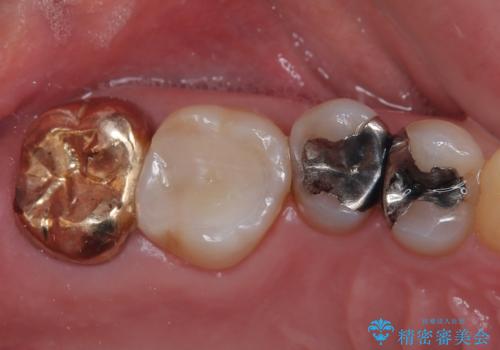

- 詰め物が欠けたとのことで来院された患者様です。来院時痛みはなく、食べ物が詰まる不快感がある状況でした。詰め物の範囲が大きくセラミックの被せもの(オールセラミッククラウン)での治療をご提案しましたが、患者様が歯はあまり削りたくないとのことで、リスクなどを説明したうえでセラミックの詰め物(ハイブリッドインレー修復)で治療していくことになりました。

拡大鏡視野下で、保険のプラスチック、虫歯の除去を行い、ハイブリッドインレーに適した形に整えました。

歯と歯茎の間に圧排糸と言われる糸を入れてシリコーン印象材にて精密な型どりをしました。